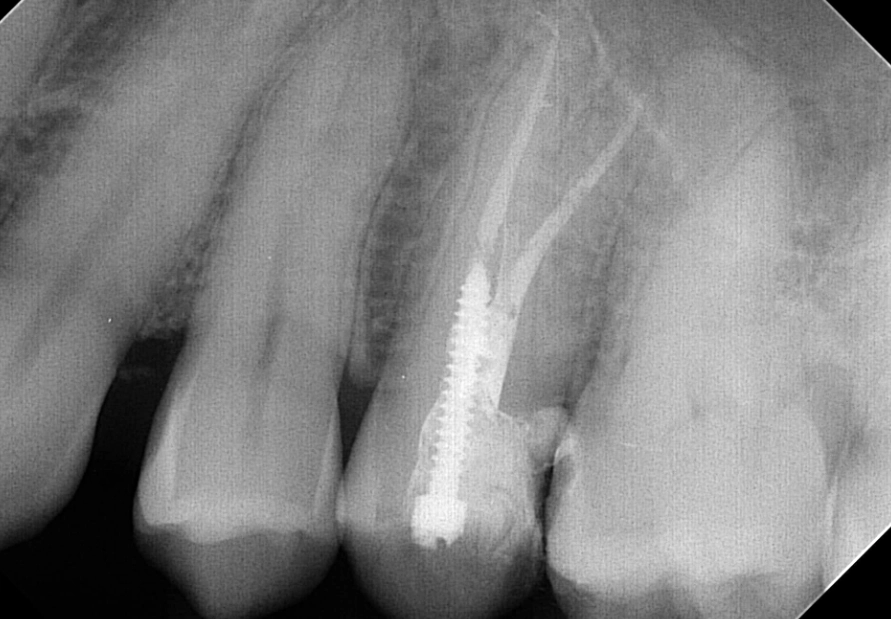

Access and Cleaning: A small opening is made in the top of the tooth. Using very fine files, the dentist removes the diseased pulp and meticulously cleans and shapes each canal. This is where the microscope is a game-changer. It allows the clinician to see intricate details, find hidden canals, and ensure no debris is left.

Disinfection and Filling: The canals are flushed with antimicrobial solutions. Once dry, they are filled with a rubber-like material called gutta-percha, sealed in place with a biocompatible cement. The goal is to hermetically seal the space to prevent re-infection.

The Temporary Fill: The access hole is closed with a temporary filling. The entire process for a premolar typically takes 60 to 90 minutes, sometimes split over two visits if there's a significant infection that needs time to drain.

For almost every premolar, you will need a dental crown. This cap encases the entire tooth, protecting it from fracture and restoring its function for chewing. Sometimes, if a lot of tooth structure is missing, a post may be placed inside the canal to help anchor the crown. Don't delay this step. Schedule your crown appointment within a few weeks of the root canal.